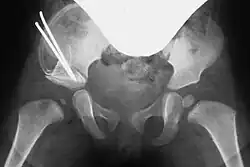

Acetabuloplasty, Step 4: Optional fixation with a Kirschner wire

In both techniques, a suitably shaped bone wedge is inserted into the resulting gap under X-ray guidance. If needed, the wedge can be fixed with an osteosynthesis wire (Kirschner wire). The procedure typically takes 45 to 60 minutes for an experienced surgeon.[3][11]